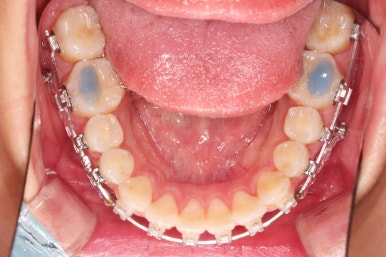

부산연산역치아교정 치료한지 5개월째 사진입니다.

빠른 시일 내에 가지런하게 되었고, 사랑니도 발치를 했으며, 통째로 뒤로 밀어주기 위한 미니스크류 세팅도 끝난 상황입니다.

주기적으로 내원하면서 뒤로 당기는 힘 조절만 해주면 되는 단계입니다.